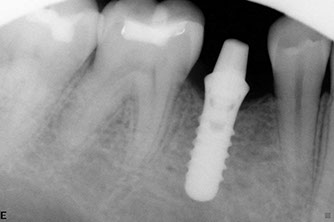

Dental implants

Dental implants have been used for decades to provide a stable support for missing teeth. Implants can be used to stabilize dentures, act as anchors for a bridge, or replace single teeth that are missing.

Implants are designed to be incorporated into the structure of the jawbone. A crown is then attached to the implant to function as a normal tooth. In most cases, implants take several months from placement to the final restoration(s). There is a period of healing while the implant becomes part of the body and stabilizes.